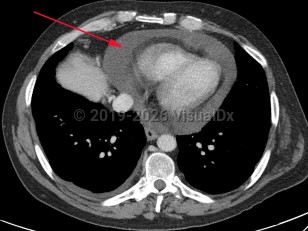

Pericardial effusion

A pericardial effusion (PE) is an accumulation of an abnormal amount of fluid within the pericardial cavity, usually from inflammation. It may be caused by local or systemic disorders or may be idiopathic. It is typically secondary to injury to the pericardium, such as pericarditis. In more than half of cases, PE is associated with a known or suspected underlying process.